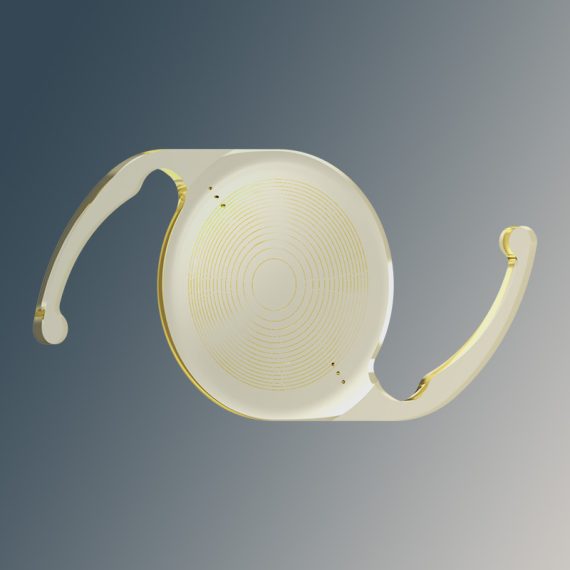

Ophtec Precizon GoOphtec’s Precizon Go is a true non-diffractive monofocal plus...Code: Explore

Ophtec Precizon GoOphtec’s Precizon Go is a true non-diffractive monofocal plus...Code: Explore -

Ophtec Precizon PresbyopicOphtec’s Precizon Presbyopic is a presbyopia-correcting IOL designed to...Code: Explore

Ophtec Precizon PresbyopicOphtec’s Precizon Presbyopic is a presbyopia-correcting IOL designed to...Code: Explore -